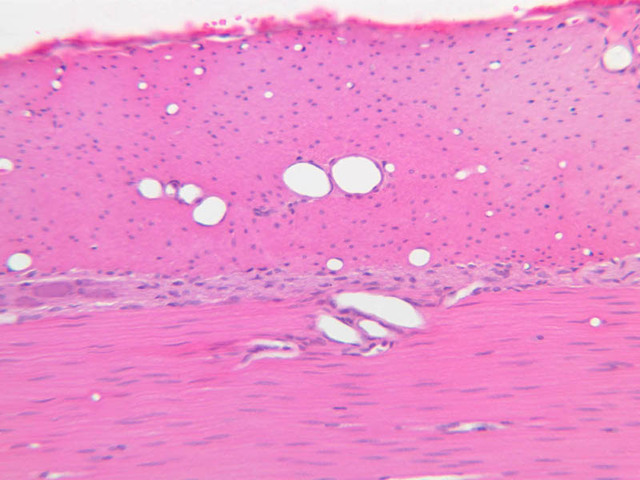

The structure of sinusoids can be studied in the liver (B-29, H&E [10x, 20x, 40x] [10x-labeled, 20x, 40x-labeled]; B-30, H&E [10x, 20x, 40x]; B-35, PAS [10x, 20x, 40x]) where they occur as endothelial tubes between plates of hepatocytes. In the liver, they are channels slightly larger in diameter than red blood cells and the individual lining cells have open spaces between them. The principal difference between sinusoids and capillaries is size, which presumably allows blood to flow more slowly in the larger sinusoids.